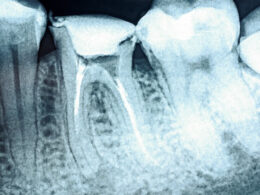

A estomatologia é a área responsável por diagnosticar doenças bucais e que, também, integra diversas especialidades odontológicas, assim como conhecimentos da medicina.

O objetivo da estomatologia é prevenir, diagnosticar, realizar tratamentos e prognósticos de “doenças próprias do complexo maxilo-mandibular, das manifestações bucais de doenças sistêmicas e das repercussões bucais do tratamento antineoplásico”, como explica o documento de consolidação das normas para procedimentos nos conselhos de odontologia.

- realização ou solicitação de exames complementares, necessários ao esclarecimento do diagnóstico.